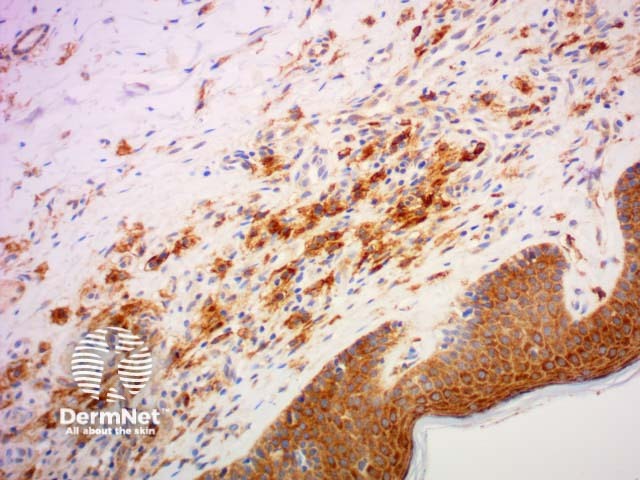

HMB 45 |

Used to detect melanocytes, especially in melanoma but negative in desmoplastic melanoma |

Melan-a |

Can help identify melanocytic naevus cells and melanomas |

HMB45

Melan A